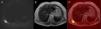

The patient is a 41-year-old woman with diagnosis of thymic carcinoma, treated with chemotherapy and radiotherapy. Chest CT showed an anterior mediastinal mass that did not modify after treatment. Later, the patient underwent thoracic MR that showed no signs of activity of the mediastinal mass with either contrast or diffusion restriction. Another mass was observed, however, in the right lower subscapular region between the scapula and the chest wall. The mass was associated with a low intensity signal in T1 and T2 and a moderately heterogeneous and intense restriction in the diffusion-weighted sequences (Fig. 1). The mass was stable when compared with previous exams. The histopathologic exam demonstrated striations of fatty tissue that alternated with fibrous tissue. The hypertrophic fibrous tissue contained fibrillar material with staining identical to the necrotic fibrous tissue, muscle and fat. These findings were compatible with ED.

(A) Diffusion-weighted sequence (b value=600) showing a mass with intense restriction in the right lower subscapular region between the scapula and the chest wall. (B) The mass is characterized by a moderately heterogeneous isointense signal in T2. (C) The fusion of the diffusion-weighted sequence in T2 demonstrates more clearly the intense restriction in the mass.